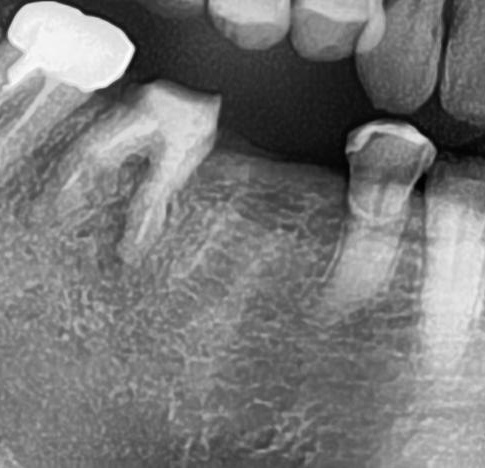

今回の患者様はインプラント植立を希望され、右下5番目の植立が決まりました。

しっかりとインプラント埋め込まれた後は、動揺がないか、噛んだ時に当たらないかなどを確認して、最後にパノラマ写真を撮影して今回のオペは終了となりました。